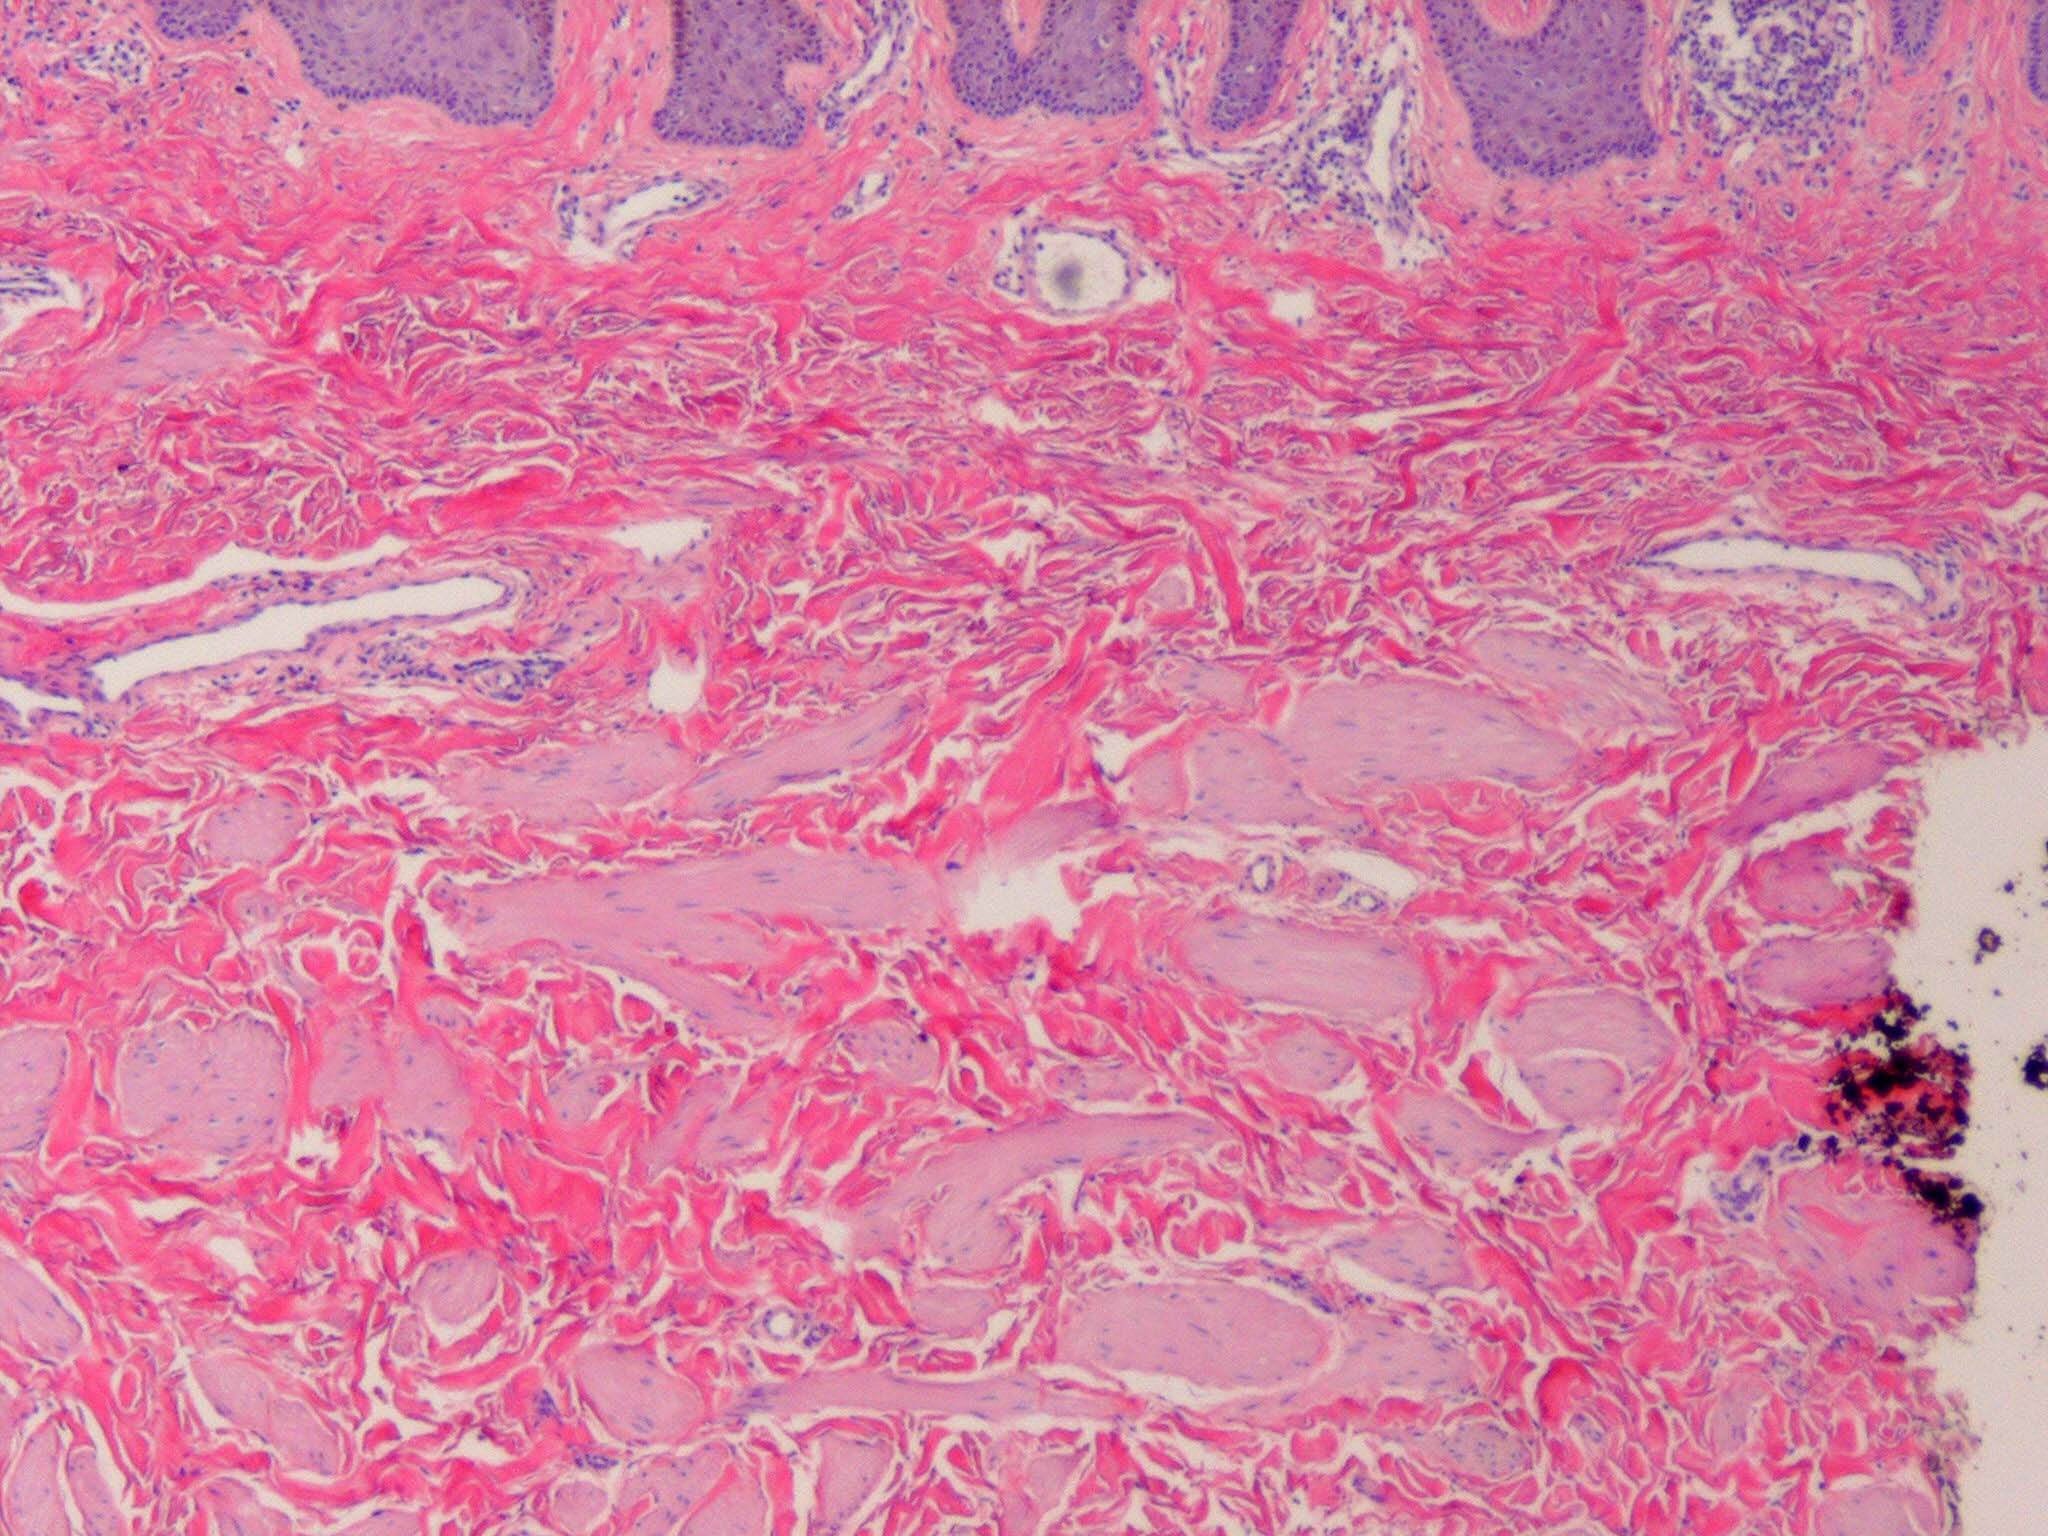

Accessory Nipple

The histologic features of a supernumerary nipple are identical to that of the regular nipple, including hyperpigmentation, slight hyperkeratosis with epidermal thickening, pilosebaceous structure of Montgomery areolar tubercles, smooth muscle bundles typical of the areola, and possible mammary glands and intradermal straight ducts.37 A significant increase in the number of clear cells of Toker has been found in supernumerary nipple tissue, indicating supernumerary nipple may be a precursor of extramammary Paget disease